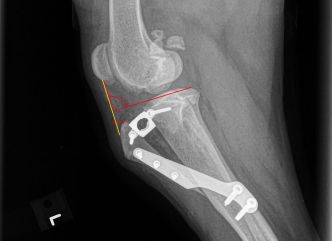

Through x-rays and tests, we learned that Jeep tore her CCL which is a ligament (much like a rubber band) that allows her knee to bend. (It is similar to the ACL ligament in people.)

Tomorrow Jeep will have a special type of surgery to repair the damage. A cut will be made into her tibia (shin) bone to separate it into two pieces then a screw will be placed in between to allow the knee to move in alignment. A bone plate will then be attached to the screw to stop it from moving. Then Jeep ‘s leg will be stitched up and she can come home. In 6-8 weeks her bone will grow around the metal pieces to give her a strong knee once more.